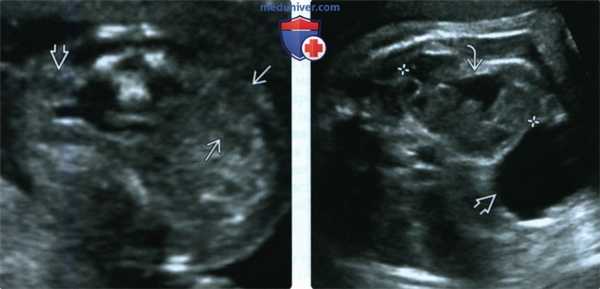

(Слева) УЗИ плода в 19 нед., поперечный срез через почечные ложа. Единственная почка. Петли кишечника, заполняющие противоположное почечное ложе, можно ошибочно принять за почку. Пустое почечное ложе -первый признак эктопии почки; на ранних сроках беременности эктопическую почку трудно обнаружить.

(Справа) Эктопия почки может сочетаться с аномалиями почки. В данном случае имеется незначительная пиелэктазия и незавершенный поворот почки. Почечная лоханка ориентирована кпереди и вбок (мочевой пузырь).

2. УЗИ при эктопии почки плода:

• УЗИ в режиме серой шкалы:

о Пустое почечное ложе:

- Надпочечник заполняет пустое почечное ложе:

Симптом «лежащего» надпочечника

- Петли толстой кишки в почечном ложе могут иметь вид почки

- У 37% плодов с односторонним запустеванием почечного ложа в действительности имеется эктопия почки

о Эктопия почки:

- В начале II триместра обнаруживается с трудом:

Эхогенность как у кишечника

В среднем диагностируется в 25 нед.

- Почка может прилежать к крылу подвздошной кости или к мочевому пузырю

- Морфология почечной паренхимы лучше визуализируется на поздних сроках беременности

- Находят гипоэхогенные почечные пирамиды

- Можно обнаружить сопутствующую почечную патологию:

Рефлюкс

Обструкция лоханочно-мочеточникового сегмента

Кистозная дисплазия из-за хронической обструкции

МКДП

- Компенсаторную гипертрофию противоположной почки не наблюдают:

Исключение - функционально неактивная эктопическая почка